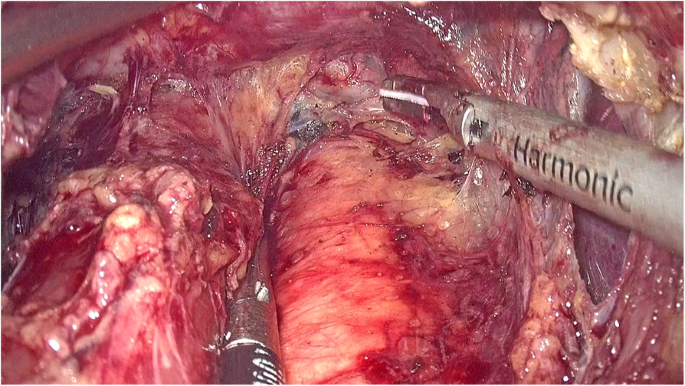

The left gastric artery was classified and ligatured. Afterwards, the abdominal esophagus was exposed circumferentially by the phrenoesophageal ligament. Both sides of the crus were cut open to release the cardia esophagus. During the operation, the right pericardial (No. 1), left pericardial (No. 2), and lesser curvature (No. 3) lymph nodes were thoroughly removed. The laparoscopic dissection of the mediastinal lymph nodes was obstructed by the diaphragm around the lower esophagus. A 5–7-cm incision was made routinely in the diaphragmatic crus (Fig. 1, Supplementary video 1), and an abundant working space was created to enhance the view of the mediastinal space. After dissection of the muscle fibers of the esophageal hiatus cross-section, the thoracic aorta was exposed. The esophageal artery was classified and confirmed during dissection of the posterior layer of the esophagus. The dissection of the left side of the distal esophagus and anterior esophagus was conducted down to the level of the tracheal bifurcation. The surgeon incised the left parietal pleura close to the pericardium. Afterwards, the surgeon opened the left thoracic cavity to the mediastinal space. The incision was extended to the left pulmonary aortic arch and hilum, leading to a large surgical field. In this manner, the lower thoracic esophageal (No. 110), supradiaphragmatic (No. 111), and posterior mediastinal (No. 112) nodes were dissected (Fig. 2, Supplementary video 1). The transection plane of the esophagus was determined through intraoperative endoscopy. A 60-mm articulating endoscopic linear stapler was used to transect the esophagus 5 cm above the proximal margin (Fig. 3, Supplementary video 1). Intraoperative frozen pathology studies were routinely conducted.